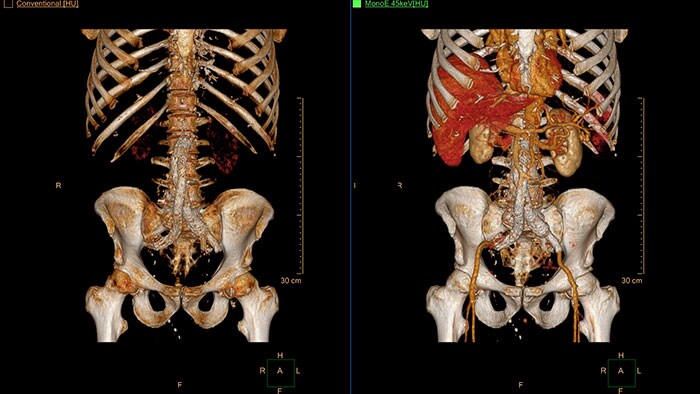

Funkcja tomografu IQon Spectral CT

IQon Spectral CT jest jedynym tomografem wyposażonym w aplikacje CT Spectral Light Magic Glass oraz CT Spectral Magic Glass on PACS, które ułatwiają radiologom przeglądanie i analizowanie wielu warstw danych spektralnych jednocześnie, także z poziomu systemu PACS.

Funkcja tomografu IQon Spectral CT*

Przeglądarka danych spektralnych (Spectral Viewer) jest aplikacją zoptymalizowaną pod kątem analizy zestawów danych spektralnych uzyskanych za pomocą tomografu IQon Spectral CT. Zapewnia łatwy i szybki wgląd w dane każdego pacjenta oraz umożliwia przeprowadzanie pomocnej w diagnostyce szybkiej oceny ilościowej. Aplikacja ta powstała z myślą o zaspokojeniu potrzeb w zakresie ogólnej wizualizacji danych spektralnych. Ponadto zapewnia dodatkowe narzędzia pomocne w analizie obrazów CT.

* W wyniku rekonstrukcji obrazu w tomografie IQon CT powstaje pojedynczy obiekt DICOM zawierający informacje wystarczające do analizy retrospektywnej — bazowy obraz spektralny (ang. Spectral Base Image, SBI). Obraz SBI zawiera wszystkie wyniki analizy spektralnej, nie ma więc konieczności przeprowadzania dodatkowej rekonstrukcji czy post processingu danych. Aplikacje do analizy spektralnej wykorzystują obraz SBI do uzyskania różnych wyników spektralnych.